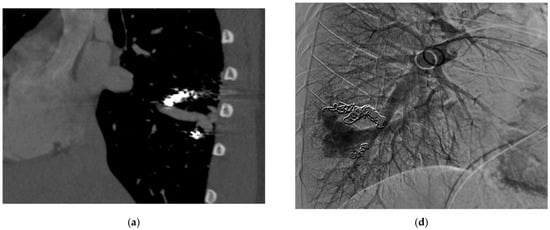

Figure 3.

An 18-year-old male with HHT with a diffuse RLL PAVM with at least four feeding arteries previously embolized. Now presents with recurrence identified on surveillance CT. (a,b) CT of the chest, MIP saggital view, demonstrates multiple collateral pulmonary branches feeding a common outflow channel. (c) Angiogram of the right pulmonary artery, early arterial phase, shows multiple collateral arteries feeding the venous outflow, (d) seen more clearly on the late arterial phase. (e) Repeat angiogram of the right pulmonary artery after embolizing multiple feeding arteries and central venous outflow shows complete occlusion of the RLL PAVM.

These criteria were confirmed angiographically, with criteria 1 demonstrated angiographically as recanalization (Figure 2a,b). Criteria 2, combines accessory feeding arteries and pulmonary collaterals together as they are generally difficult to differentiate angiographically (Figure 3a,b). Criteria 3 is angiographically shown as perfusion of the PAVM outflow via injection of systemic arteries (Figure 4a,b).

The proposed reintervention criteria were based off the greater than 30 years of experiences at a single large HHT center of excellence. The reintervention criteria described in this paper may be used as general guidelines but may not always be generalized to each patient and practice. Additionally, as the population in this study only included adults, it may not be applicable to the pediatric population. The first indication of reintervention requires experience evaluating the embolic devices. A contrast-enhanced chest CT must be windowed in such a way to see the degree to which contrast flows through the embolic device(s). If a column of contrast is measured to be approximately greater than 2–3 mm through, this would suggest a need for reintervention (Figure 2a,b). This may be difficult to determine, and evaluation of the scout images can be helpful to see how well the coil is packed. The second indication for reintervention involves the treatment of accessory pulmonary collaterals (Figure 3a–e). Accessory pulmonary collaterals are a result of adjacent pulmonary vessels which fill the feeding artery or sac beyond the embolic device(s). When this collateral vessel is greater than 2–3 mm, reintervention is indicated. The third criteria involve the treatment of systemic collaterals (Figure 4a–c). This is by far the most complicated issue to address and was the cause of the sole case of iatrogenic stroke. Luckily these systemic collaterals are rare, with a lifetime prevalence of 1.0% [13]. The author’s institutions experience treating these systemic collaterals was previously published. Patients with previously treated PAVMs presenting with hemoptysis are often due to systemic collaterals. In some cases, these lesions can be clearly identified on a chest CTA; however, this is not always the case and therefore a clinical presentation of hemoptysis is enough to indicate reintervention and interrogation of the systemic arteries. Understanding the best way to treat these lesions is an ongoing process.